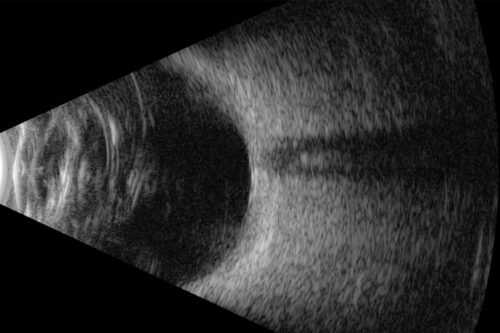

Low noise, high performance

In posterior B-Scan mode, Eye One’s industry leading signal-to-noise ratio means it’s able to detect the subtlest vitreous echoes, offering unparalleled distinction and diagnosis accuracy across the retina, choroid, sclera, and the vitreo retinal junction.